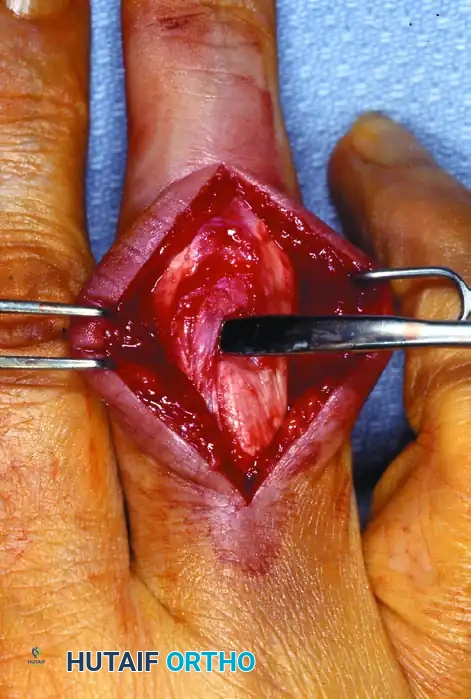

Intraoperative view following the reduction of the trapped lateral band.

- Extensor Mechanism Reflection: Identify the transverse retinacular ligament. Incise this ligament longitudinally to mobilize the lateral band. Reflect the extensor mechanism dorsally to expose the underlying joint capsule and the remnants of the collateral ligament.

2. Joint Preparation and Scar Excision

- Debridement: Inspect the joint for any osteochondral fragments or interposed soft tissue. Excise any dense scar tissue from around the anatomical origin (proximal phalanx head) and insertion (middle phalanx base) of the cord fibers of the collateral ligament.